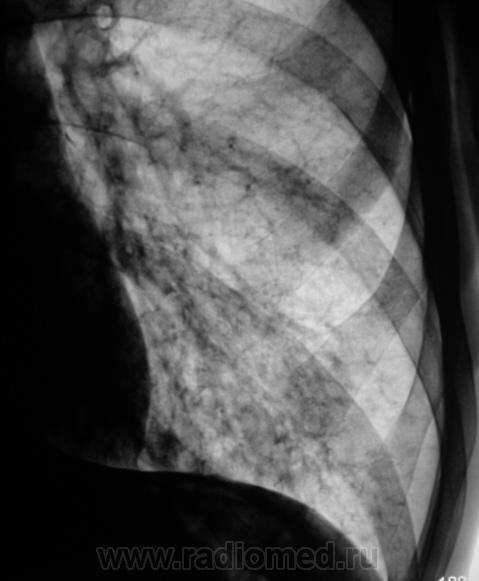

Пациент направлен на рентгенографию ОГК с диагнозом - "Левостороняя пневмония".

Анамнез стандартный. Ранее неоднократно страдал обострениями хронического бронхита. Сейчас вот не нашутку занемог - температура до 38, откашливает мокроту, кашель продуктивный.

Диагноз левосторонней нижнедолевой С10, С9 сементарной пневмонии наверное будет верным, а с учётом фона- с наличием бронхоэктазов.